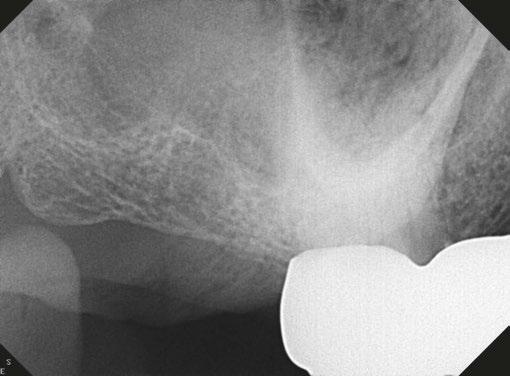

Clinical case performed by Dr. Brett Gilbert (Figures 4 and 5)

In this case, Dr. Gilbert was initially unable to locate the MB2 canal, despite thorough attempts using ultrasonic and a microscope. After performing the irrigation protocol with Odne®Clean, the MB2 became visible. Following activation, the filling material extended completely through the MB2.